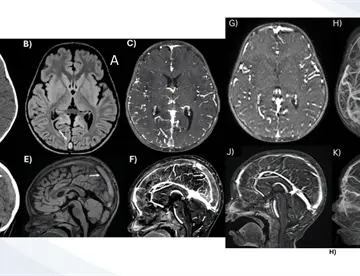

<content:encoded><![CDATA[<div><img src="https://blob.medicinaysaludpublica.com/images/2026/05/04/sacs-20--1091-6ddd317a-focus-0-0-360-276.webp" alt="¿Cómo reconocer la hipertensión pulmonar? Causas y tratamientos que pueden cambiar su pronóstico" title="¿Cómo reconocer la hipertensión pulmonar? Causas y tratamientos que pueden cambiar su pronóstico"></div><p>La <strong><a href='https://medicinaysaludpublica.com/tags/hipertension/13040' target='_blank'>hipertensión</a></strong> <strong><a href='https://medicinaysaludpublica.com/tags/pulmonar/45862' target='_blank'>pulmonar</a></strong> es un trastorno que afecta las arterias de los pulmones y el lado derecho del <strong><a href='https://medicinaysaludpublica.com/tags/corazon/12206' target='_blank'>corazón</a></strong>. En su forma más frecuente, la <strong>hipertensión</strong> arterial <strong>pulmonar</strong> (HAP), los vasos sanguíneos se estrechan, bloquean o destruyen, lo que dificulta el flujo de sangre y obliga al <strong>corazón</strong> a trabajar con una carga creciente hasta debilitarse.</p>

<p>Los síntomas —falta de aire, fatiga, mareos, hinchazón en piernas y abdomen, y presión en el pecho— se instalan de forma tan gradual que los pacientes pueden no advertirlos durante meses o incluso años.&nbsp;</p>

<p>Cuando la enfermedad está avanzada, sus manifestaciones se confunden fácilmente con otras afecciones cardíacas y pulmonares, lo que complica el diagnóstico temprano.</p>

<h1><strong>Cinco grupos, múltiples causas</font></strong></h1>

<p>La medicina clasifica la <strong>hipertensión</strong> <strong>pulmonar</strong> en cinco grupos según su origen. El más común corresponde a enfermedades del lado izquierdo del <strong>corazón</strong>, como la insuficiencia cardíaca o las enfermedades de las válvulas mitral y aórtica. Le siguen las causadas por enfermedades pulmonares crónicas —fibrosis <strong>pulmonar</strong>, EPOC, apnea del sueño— y las derivadas de obstrucciones en la arteria <strong>pulmonar</strong> por coágulos sanguíneos persistentes o tumores.</p>

<p>El grupo de la <strong>hipertensión</strong> arterial <strong>pulmonar</strong> propiamente dicha puede aparecer sin causa conocida, por herencia genética, por consumo de sustancias como la metanfetamina o la cocaína, o asociada a enfermedades autoinmunes como el lupus y la esclerodermia. Vivir a más de 2.400 metros de altitud, tener antecedentes familiares de coágulos y el sobrepeso son también factores de riesgo reconocidos.</p>